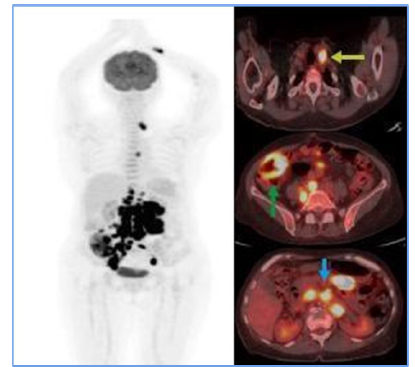

As a result, the treating hematologist recommended a second-line chemotherapy regimen (RICE) for 3 cycles. At the end of these sessions, a follow-up PET scan revealed the resolution of adenopathy in the obturator chain (Figure 3), demonstrating a complete metabolic response. Based on these findings, the patient was declared in remission. Given the favorable evolution, maintenance immunotherapy was initiated with a standard-dose Rituximab regimen for low-grade lymphoma, administered every 2 months for 2 years. As for the writing of this report, the patient has successfully completed 9 cycles and remains in remission.

Figure 2

PET CT before ICE regimen. Only the right internal iliac chain adenopathy was evident (green arrow), which showed FDG uptake, exceeding hepatic uptake about score 4 of the Deauville criteria, suggesting a partial metabolic response to the medical treatment instituted.

For staging, PET-CT (F18-FDG) is a crucial tool. Initially, it allowed for documentation of both nodal and extranodal involvement, establishing tumor viability and aiding in follow-up and evaluation of treatment response. The Deauville 5-point visual scale [7] was used to assess treatment response. In this case, the PET-CT documented persistent disease (Deauville 4), which influenced treatment decisions and led to escalation of the medical management. A subsequent PET-CT (F18-FDG) performed after rescue therapy demonstrated a complete metabolic response at the end of treatment [8].

In the case presented here, the patient showed a favorable response to chemotherapy, achieving complete remission and surviving for two years to date. Lymph node and extranodal involvement, along with immunohistochemical findings, enabled the diagnosis and timely treatment initiation (Figure 1). The partial metabolic response observed in the post-treatment PET (Figure 2) led to the decision to escalate the treatment to second-line RICE chemotherapy. Eventually, a new PET-CT (F18-FDG) post-treatment (Figure 3) confirmed a complete metabolic response.